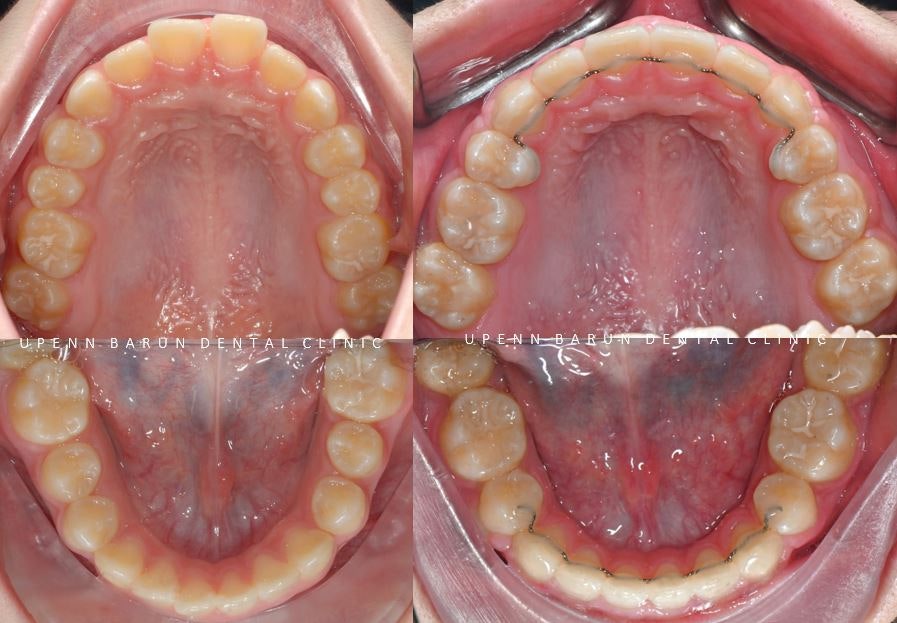

유펜바른치과에서 발치교정 후

돌출되어있던 앞니가 들어가면서 치아가 올바르게 배열되었는데요 :)

깊게 물리던 교합과

입천장에 닿고 있던 아래 앞니들이

제 위치를 찾으며

이상적인 교합으로 마무리 해드렸습니다. ^^

교정기간: 22/3~24/3

유펜바른치과에서

발치교정 완료 후

안쪽 유지장치까지 마무리 해드렸습니다 ^^